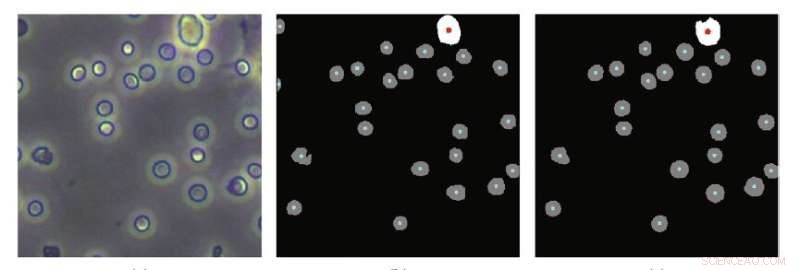

Results of cell counts compared to predicted count results showed that the newly developed training method allows machine learning to more accurately count blood cells. Credit: Cyborg and Bionic Systems

In order to improve accuracy, reduce complexity and lower costs, much research into alternatives has lately focused on the use of computer programs to perform "segmentation" on photographs of the blood taken by a high-definition camera connected to a microscope. Segmentation involves algorithms that perform pixel-by-pixel labeling of what appears in a photo, in this case, what parts of the image are cells and which are not—in essence, counting the number of cells in an image.

These single-cell-type images are "preprocessed" automatically by conventional algorithms that reduce noise in the images, enhance their quality, and detect the contours of objects in the image. They then perform adaptive image segmentation. This latter algorithm calculates the various levels of gray in a black and white image, and if a part of the image lies beyond a certain threshold of gray, the algorithm segments that out as a distinct object. What makes the process adaptive is that rather than segmenting out parts of the image segments according to a fixed gray threshold, it does this according to the local features of the image.

To test their training scheme, the researchers first used a traditional cell analyzer on the same mouse blood samples to do an independent cell count against which they could compare their new approach. They found that the accuracy of their training scheme on segmentation of multiple-cell-type images was 94.85 percent, which is the same level achieved by training with manually annotated multiple-cell-type images.